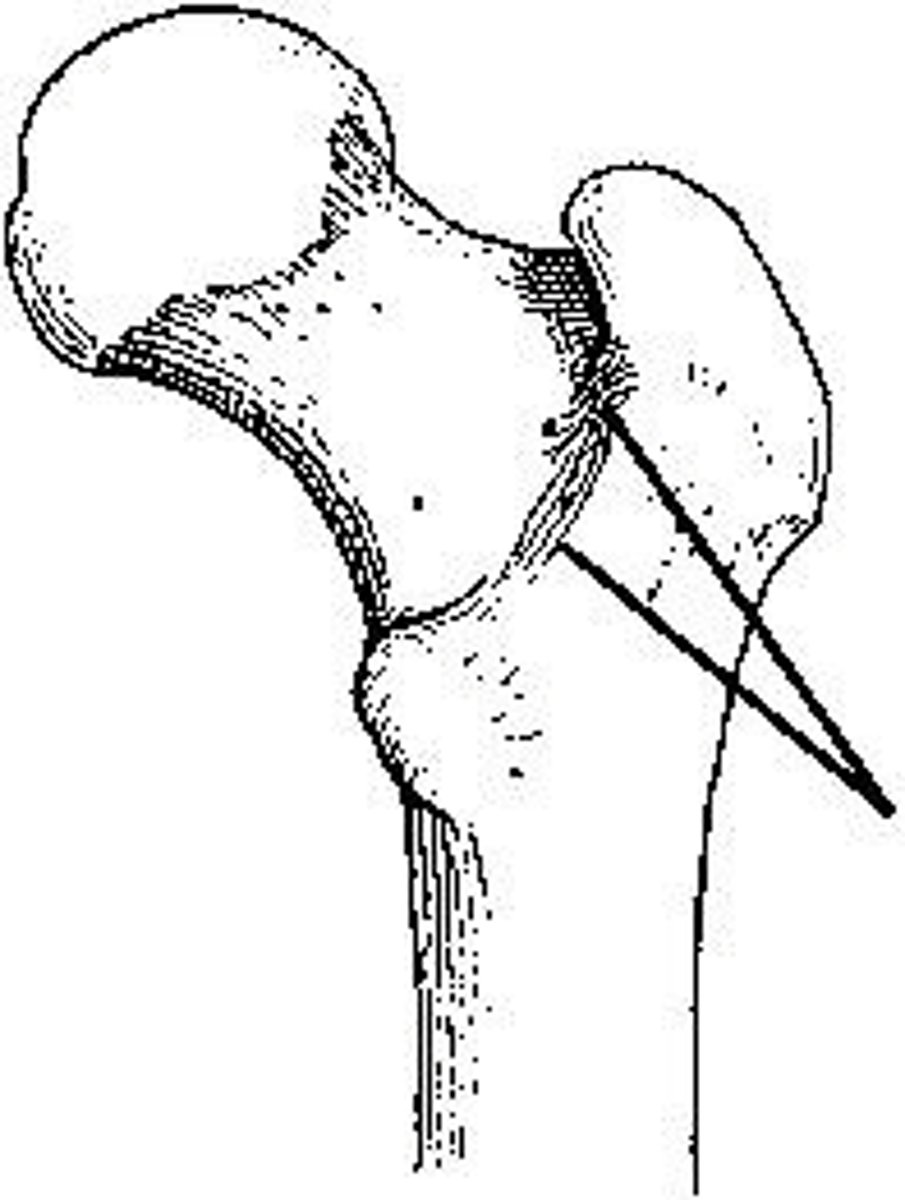

intertrochanteric crest

The area identified on the bone shown in the figure above is the: